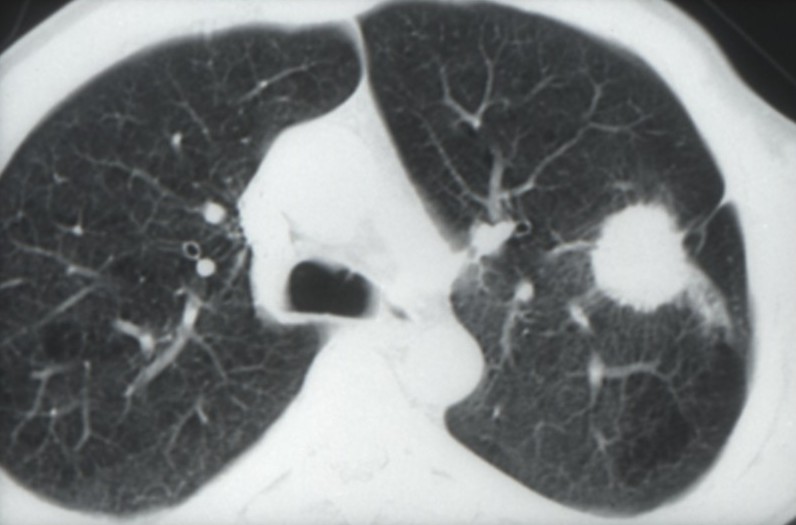

Cancers bronchiques